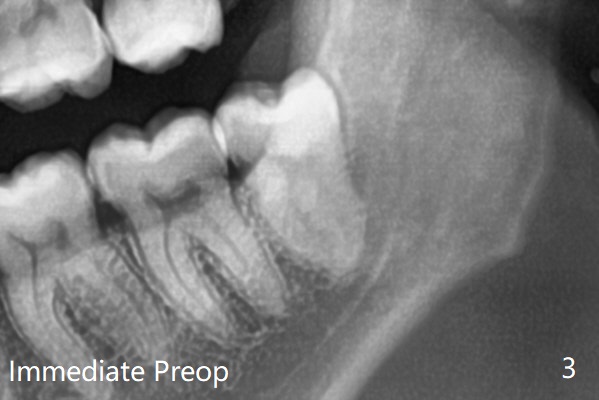

每个牙槽窝放置0.5cc骨水泥(Bone Cement (Bond Apatite from Augma)),覆盖半块胶原塞,4-0铬羊肠线缝合(图四)。